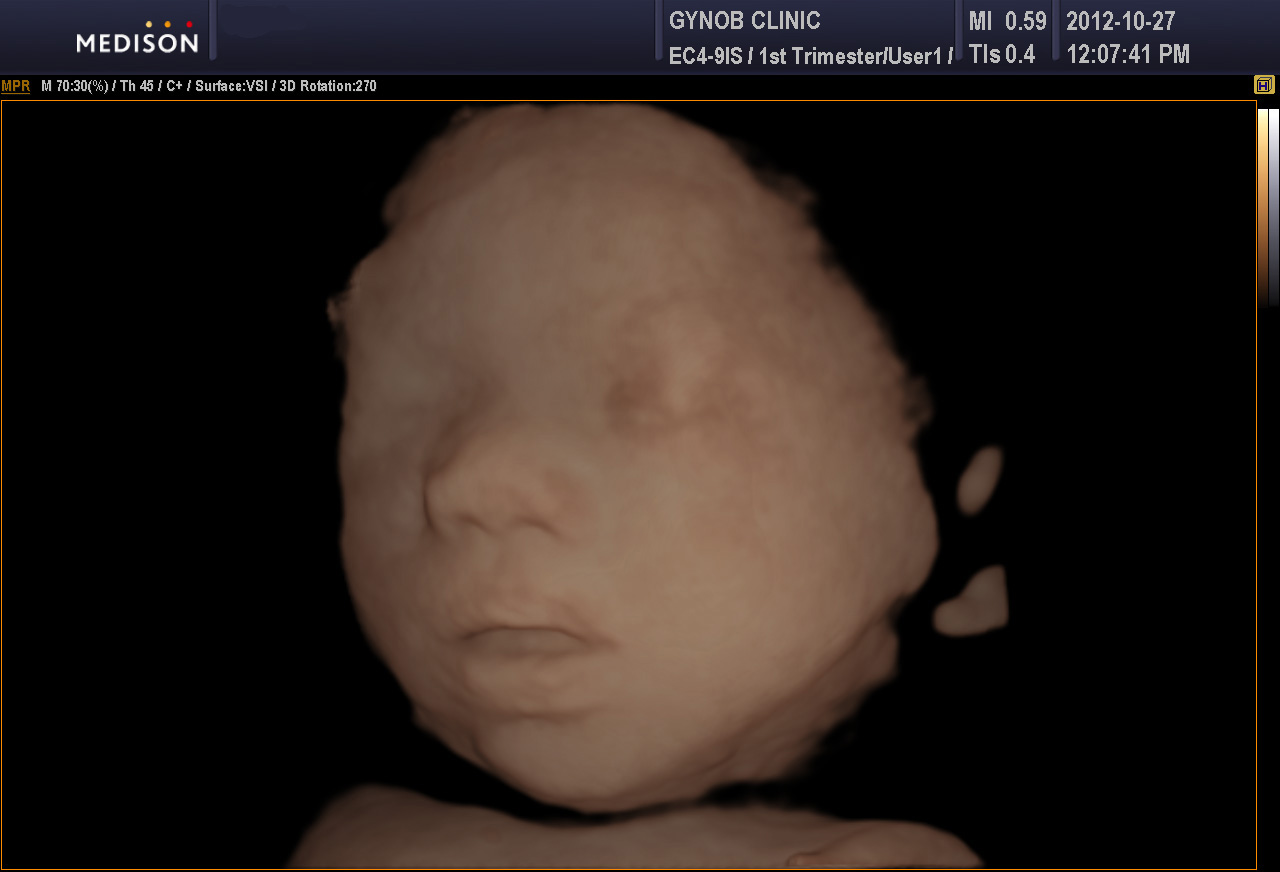

아래는 본원에서 찍은 초음파 사진으로 본 정상 태아의 입술 주변 모양입니다.

위 사진은 일반 2D 이미지 사진이고 아래는 입체 초음파 사진입니다.

구순열이 있을 경우 연속된 선이 끊어진 것으로 나타납니다.

구순열 태아의 초음파 사진을 어딘가 보관해 두었던 것 같은데 찾지 못하여 정상 사진을 올려 두는 점 양해 부탁드립니다.